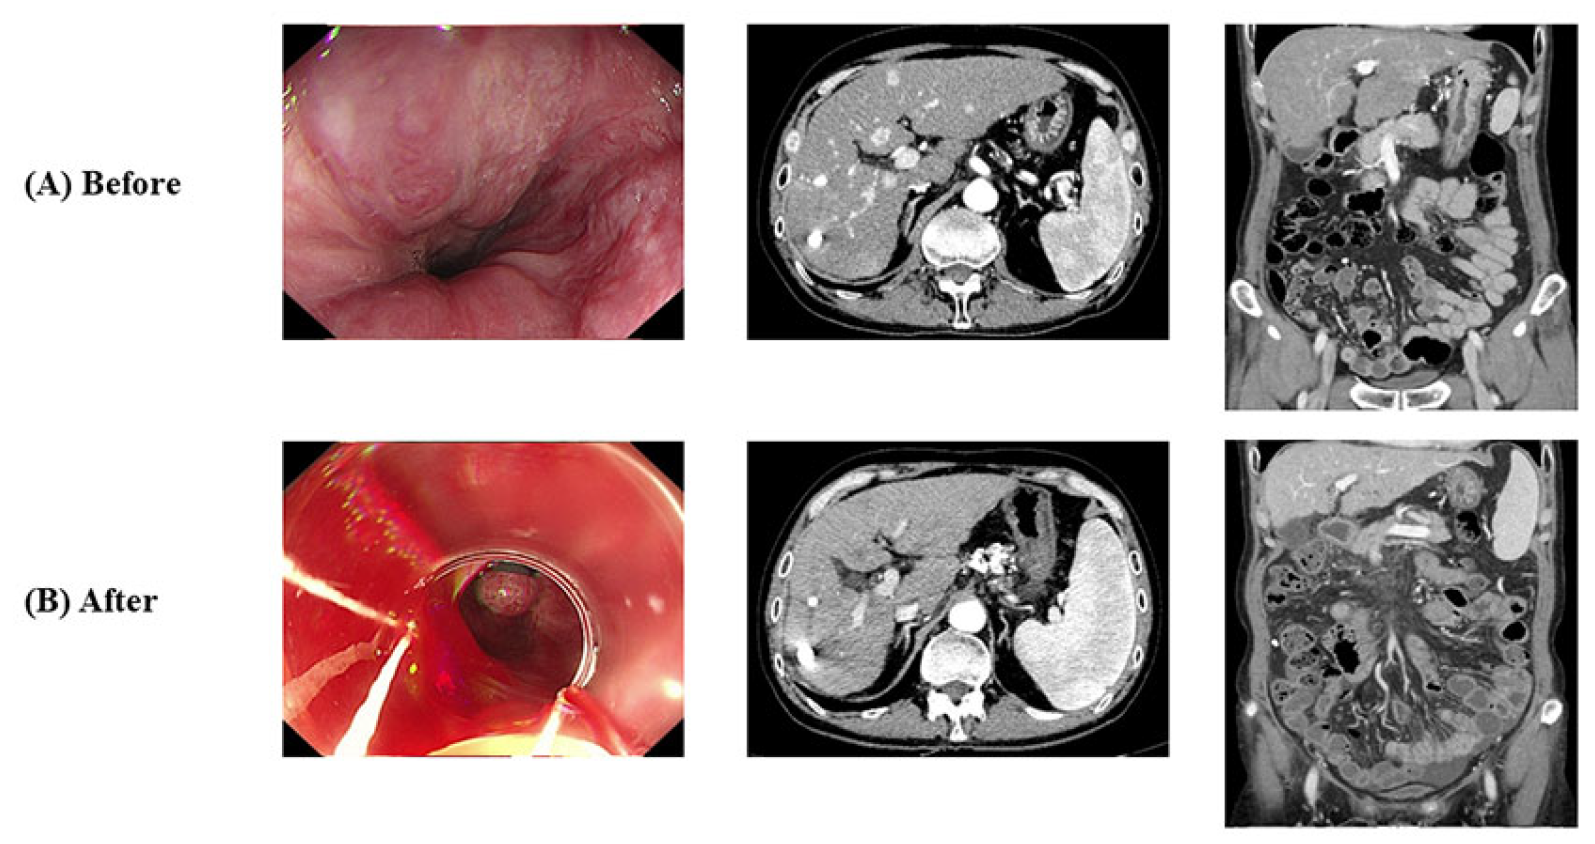

- Case 1